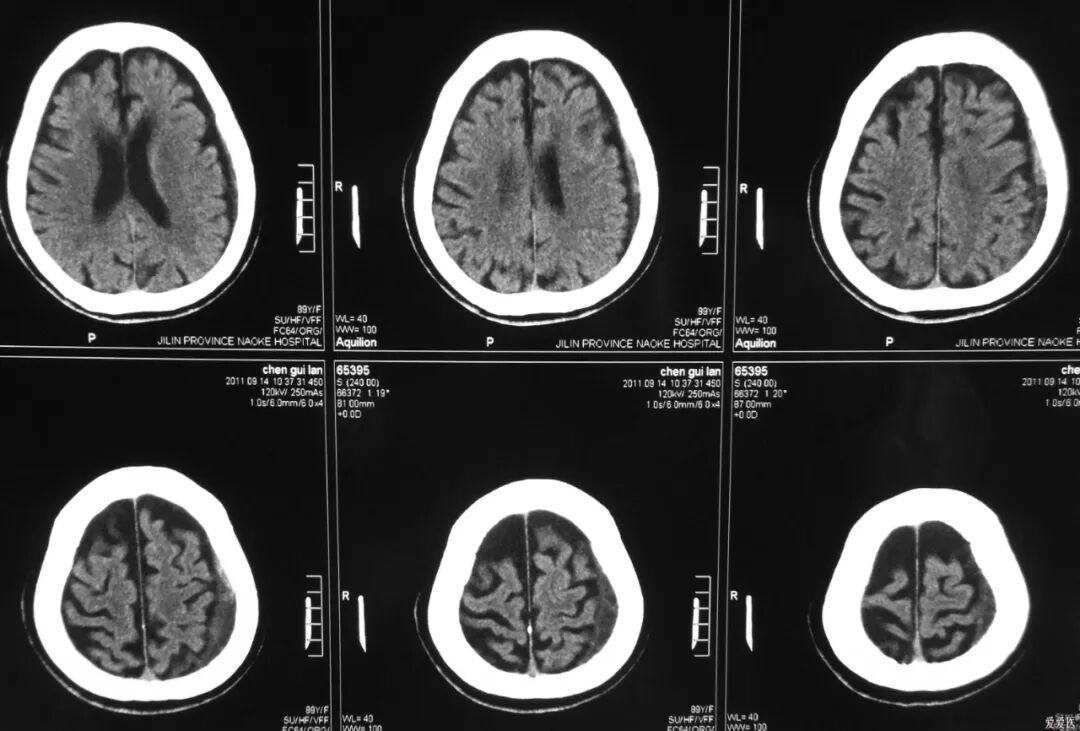

CT图像举例

dr在彩超什么意思一文搞懂X线、CT、MR、彩超检查的区别_https://www.jmylbn.com_新闻资讯_第13张

dr在彩超什么意思一文搞懂X线、CT、MR、彩超检查的区别_https://www.jmylbn.com_新闻资讯_第14张

CT检查相当于把人体切成一定间距的小段,间距可以是0.25cm、0.5cm、1cm等等,切完以后可以在图像上看到一段横切面的状态。不同的切面呈现不一样的脏器,通过扫描把人体各个部位的器官和结构拉开,使我们可以看得非常清晰。

擅长神经系统、心脏大血管疾病

可以断层看,经后期处理可以显示更多信息;

辐射剂量高;

除了肌肉、韧带含水较多以外,脑的含水量也很大,所以脑部做核磁扫描也非常清楚。